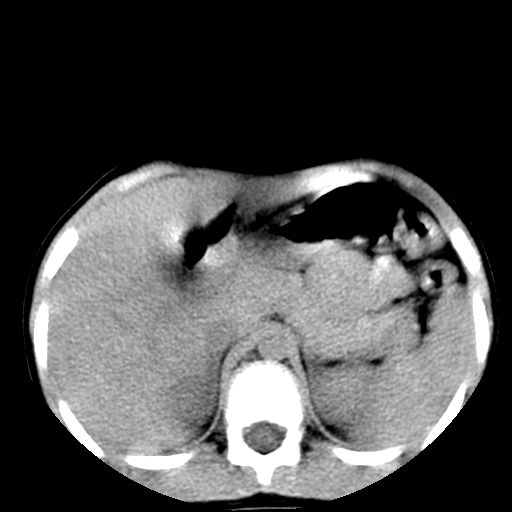

腹部好象未见异常。

腹部ct平扫未见明确异常

腹部ct平扫不能提示哪里有病变。